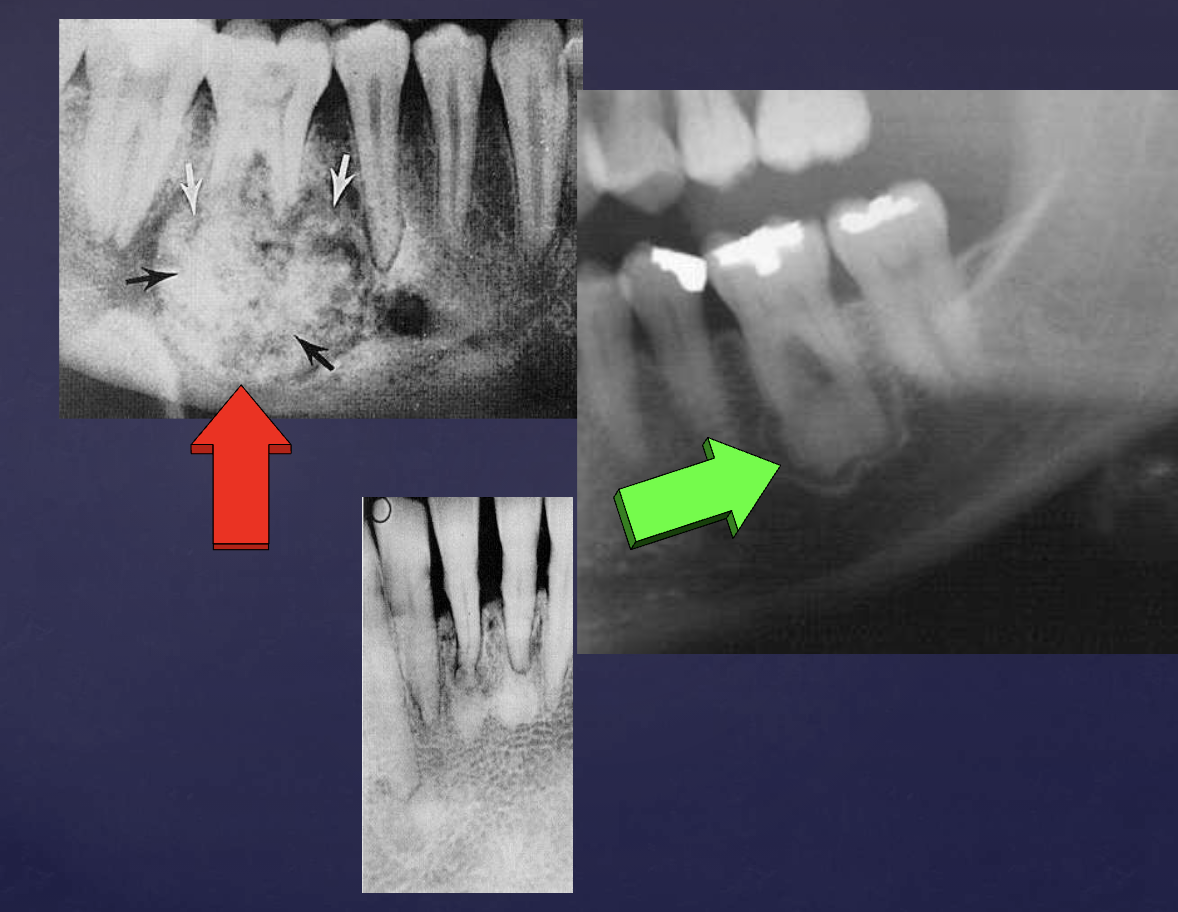

describe the ameloblastoma in this radiograph

multilocular w/ coarse septae

thinning of inferior mand border

displacement of teeth + IAN

T/F: you can see B/L expansion in this radiograph

false, since this PAN is a superimposed image- you cannot tell